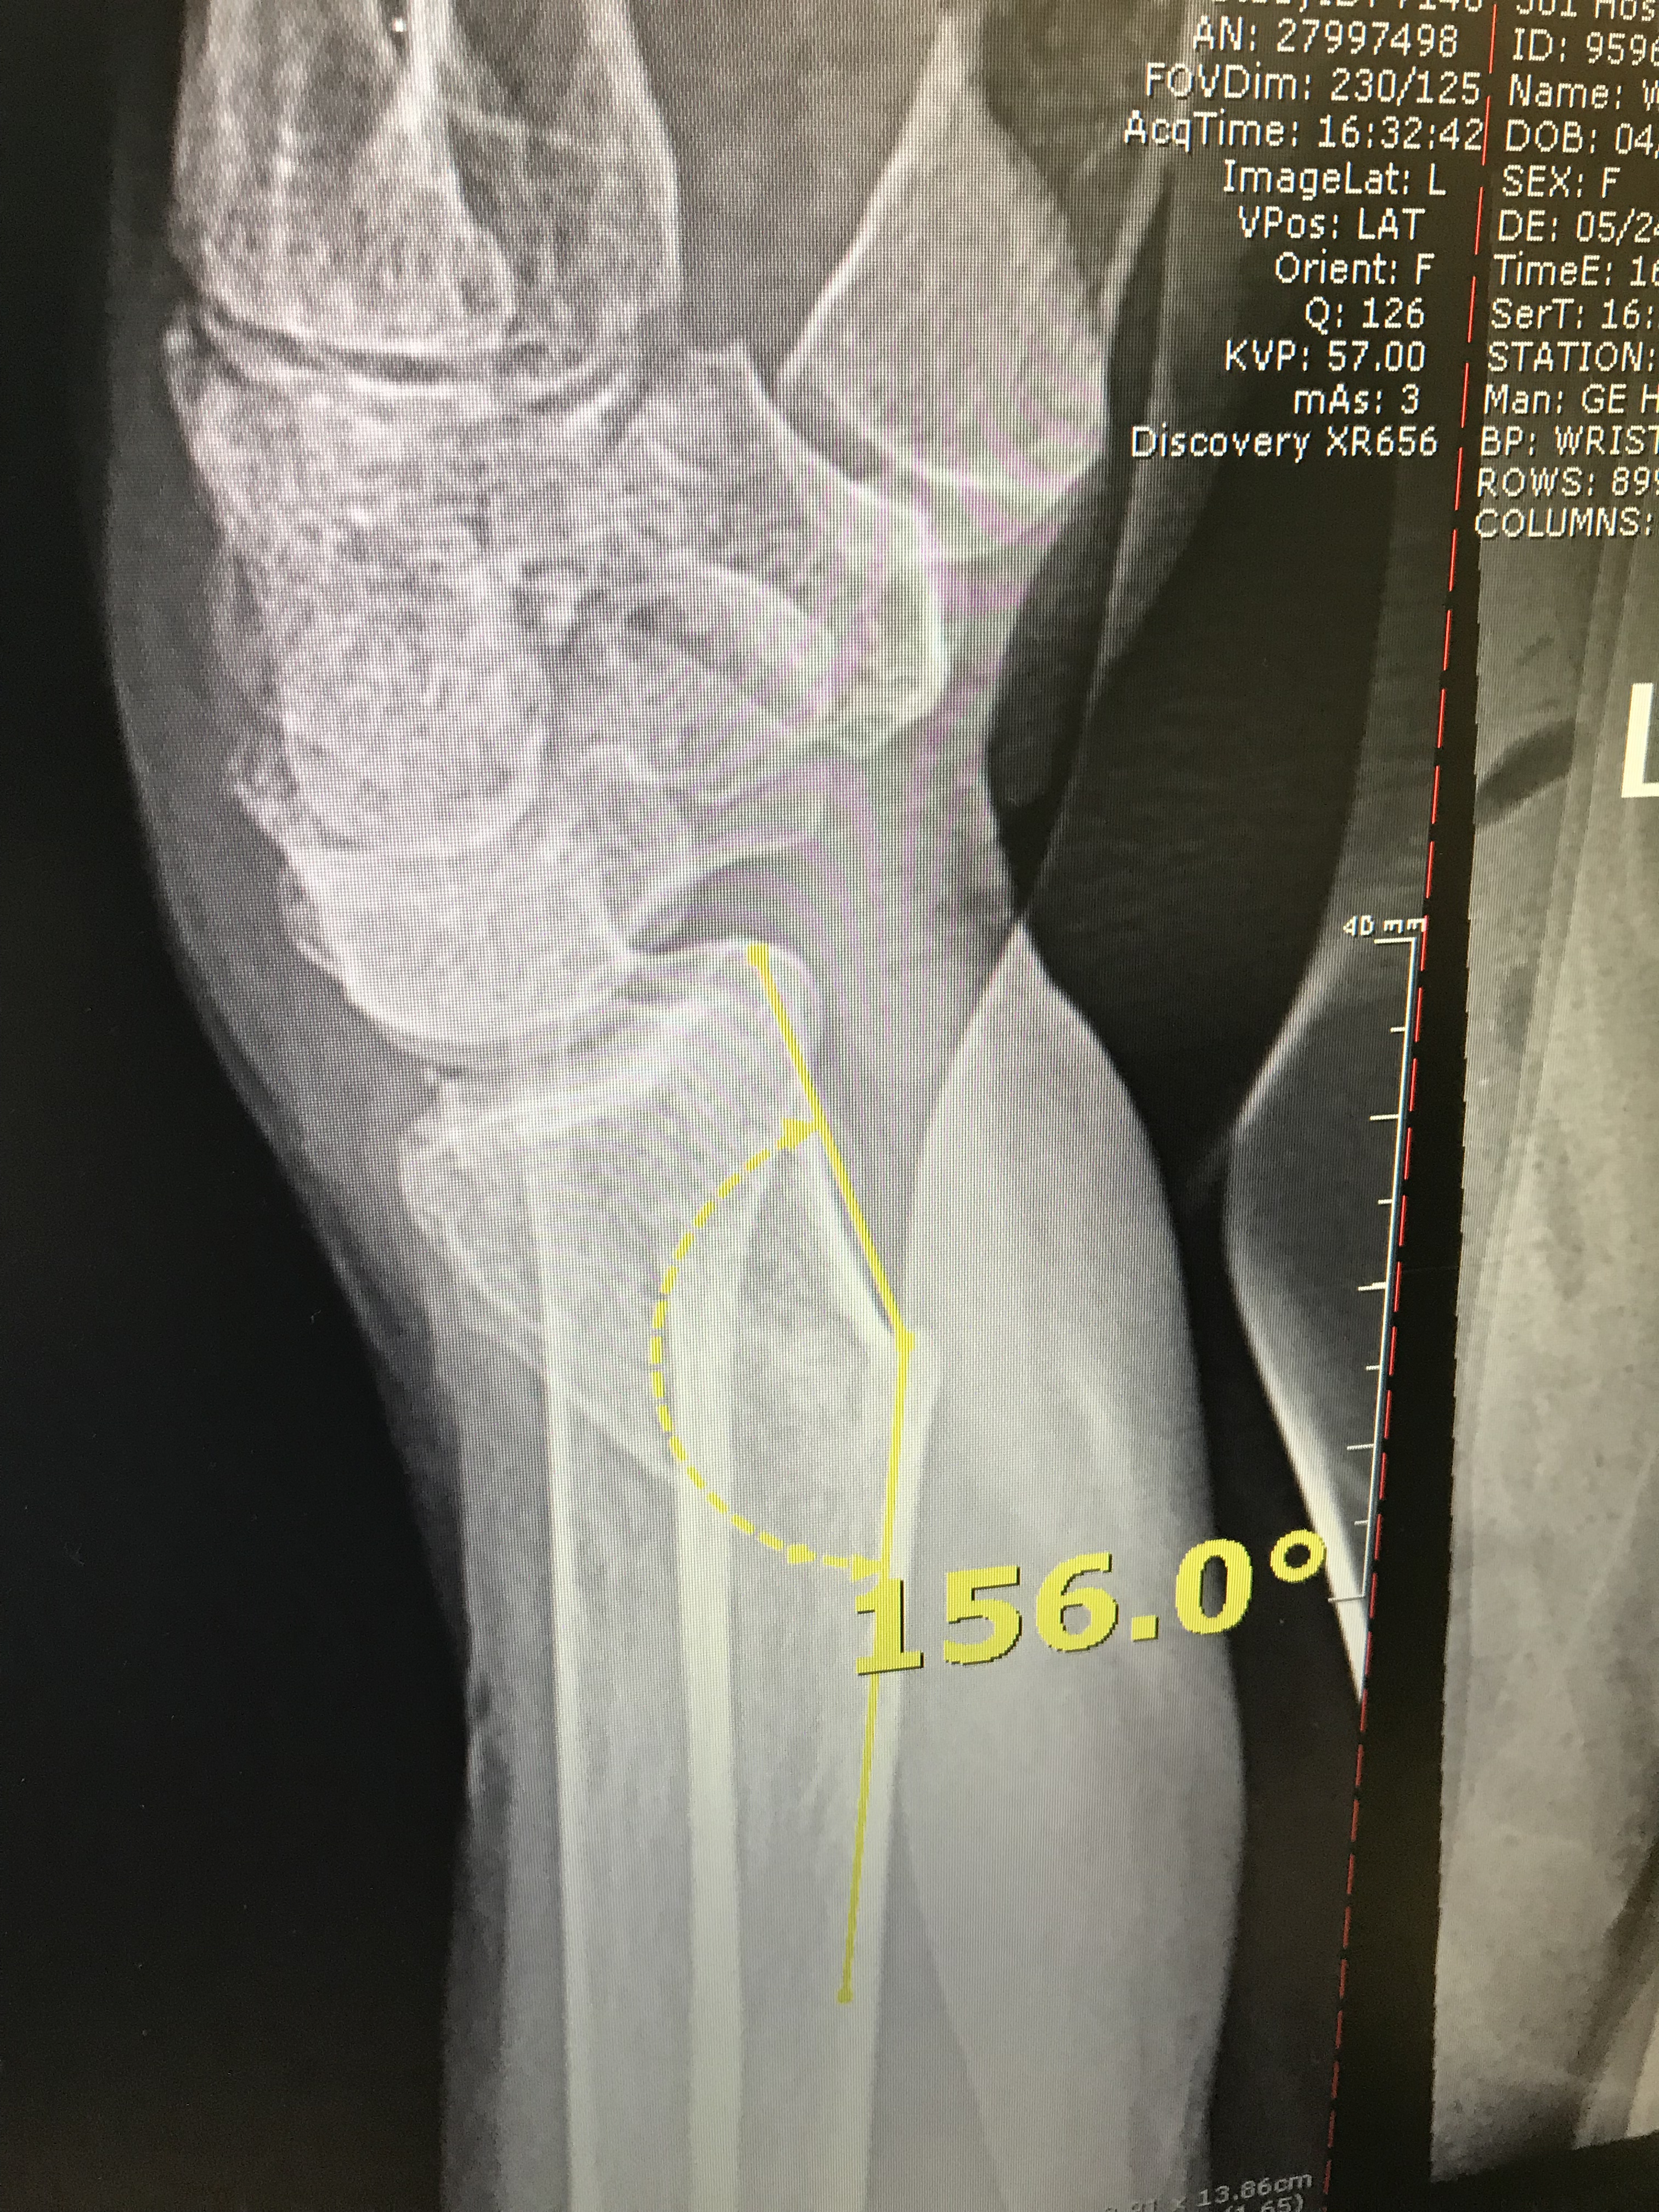

img_6464 Arden May 28, 2019May 28, 2019 Published by Arden View all posts by Arden Published May 28, 2019May 28, 2019